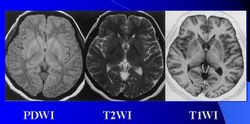

頭部質子密度成像,T1、T2像MRI在臨床上主要用於以下部位:①頭部。可清晰分辨腦灰質和白質,對多發性硬化等一類脫髓鞘病優於CT。對腦外傷、腦出血、腦梗塞、腦腫瘤等同CT類似,但可顯示CT為等密度的硬膜下血腫。腦梗塞或腦腫瘤的早期,CT不能查出,而MRI有可能顯示。對鈣化和腦膜瘤顯示不好。腦幹及小腦病變的MRI圖像由於沒有偽影是首選檢查方法。②脊柱。不需要造影劑就能清晰區分脊髓、硬膜囊和硬膜外脂肪。對腫瘤、脊髓空洞症、脫髓鞘病變等均有較高診斷價值。顯示骨折或脫位不如常規X射線或CT,但能觀察脊髓損傷情況。顯示椎間盤較好,可以分辨纖維環和髓核,特別是矢狀面圖像可以同時顯示多個椎間盤突出。③四肢。對骨質本身病變顯示不如常規X射線或CT。對軟組織及肌肉病變包括腫瘤及炎症都能清晰顯示,特別是對早期急性骨髓炎,是一種靈敏度很高的檢查方法。也是檢查膝關節半月板病變的首選方法。④盆腔。對直腸及泌尿生殖系統優於CT,無輻射損害,特別適用於孕婦及胎兒檢查。⑤胸部。對肺的檢查不如常規X射線,對縱隔檢查則優於CT,不用造影劑即可分辨縱隔血管和腫物,也是一項有價值的心血管檢查技術。⑥腹部。主要用於肝、胰、脾、腎等實質臟器。